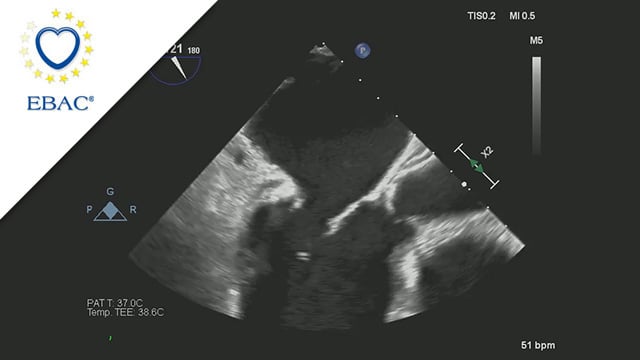

A 78-year-old male presents with recurrent hospitalisations for HFpEF and severe degenerative MR. Multimodality imaging reveals fibro-calcific leaflet disease, restricted motion, and a short posterior leaflet, making him a suboptimal candidate for M-TEER and prompting consideration of transcatheter mitral valve replacement. How would you treat?